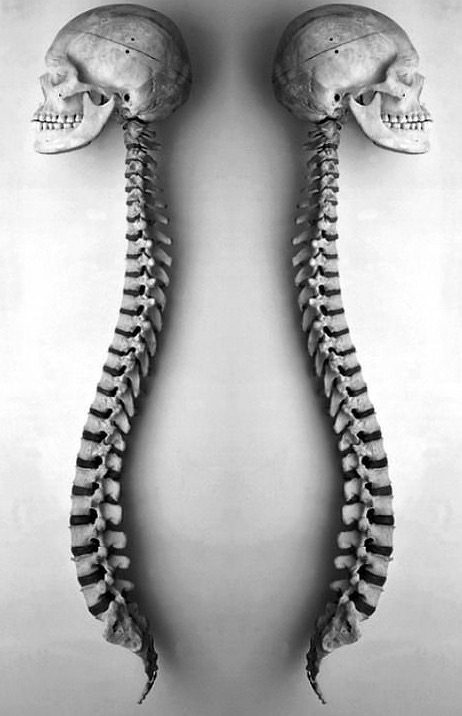

人体从什么时候开始拥有了4个生理弯曲,首先成年人脊柱有4个生理弯曲,即颈曲、胸曲、腰曲和骶曲。其中颈曲和腰曲凸向前,胸曲和骶曲凸向后,这样记忆比较好,一前一后。颈椎超前凸起,胸椎朝后凸起,腰椎向前凸起,骶椎朝后凸起,就这样一前一后的形状排列。人类脊柱的生理弯曲,是在漫长的进化过程中形成的这4个生理弯.....

脊柱,也被称为脊柱或脊椎骨,是我们身体的中心支柱。 它的主要作用之一是引导躯干允许我们做的许多动作:弯曲、伸展、旋转、倾斜。它由24个椎骨组成:7个颈椎骨,12个胸椎骨和5个腰椎椎骨,5个骶骨椎骨和3 - 5个尾骨椎骨。像所有的关节一样,椎骨是由许多韧带和肌肉连接在一起的。它们由一个椎间盘隔开,椎.....